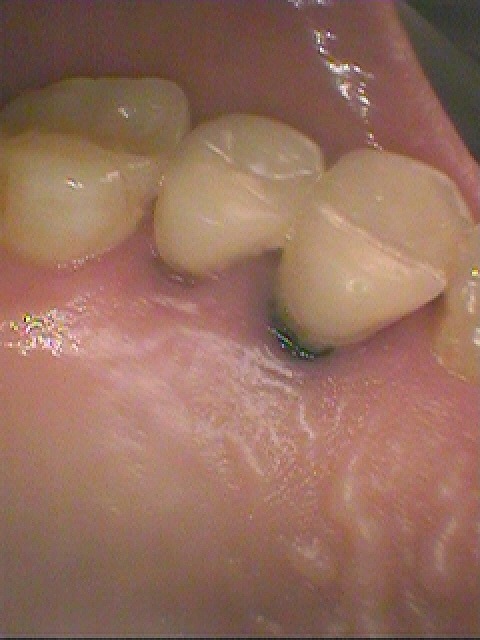

術前の口腔内になります

4番部が噛むと痛むそうです

動揺もありました

根元も黒く悪くなっていました